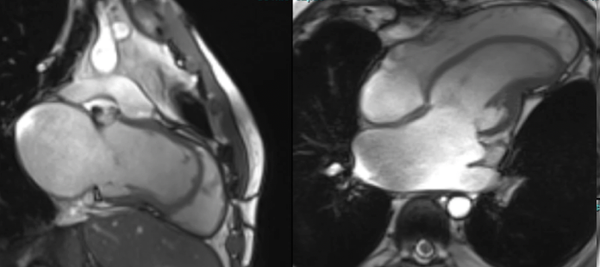

Dilated cardiomyopathy